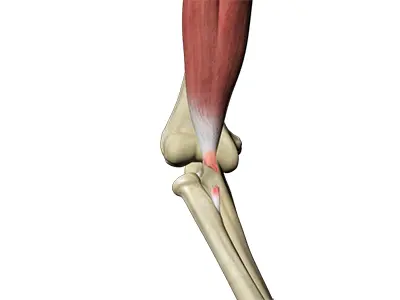

Distal Biceps Repair

The biceps is a large muscle located in the front of your upper arm and runs from the shoulder to the elbow joint.

Biceps Tendon Repair

Biceps tendon repair is a surgical procedure to restore a biceps tendon that has been torn or ruptured by severe trauma or injury.

Bicep Tendon Tear at the Elbow

A biceps tear can be complete or partial. Partial biceps tendon tears will not completely break the tendon while complete tendon tears will break the tendon into two parts.

Distal Biceps Injuries

The biceps is a large muscle present in front of the upper arm, extending from the shoulder joint to the elbow.

Distal Biceps Avulsion

The biceps muscle, located in the front of the upper arm, allows you to bend the elbow and rotate the arm.